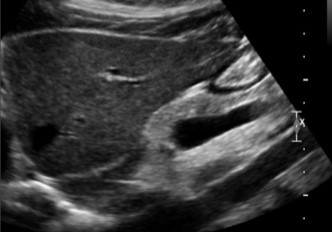

This image was taken in what plane?

Explain your answer.

Sagittal

The pancreas head is the only part visualized